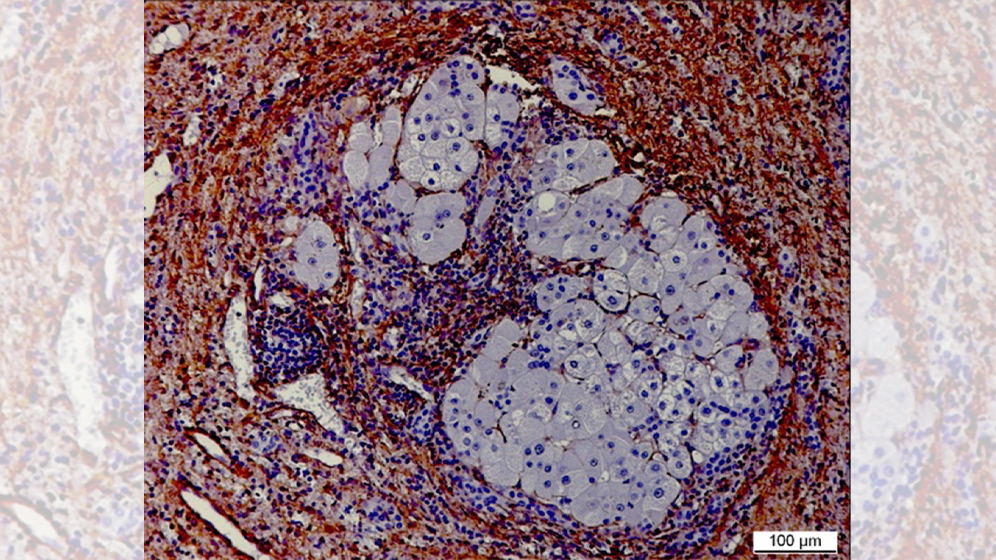

Die Wissenschaftler untersuchen strukturelle Veränderungen der extrazellulären Matrix und der Zellinteraktion in sogenannten zirrhotischen Knoten, die als Kipppunkt (TIP) die Entstehung eines HCC begünstigen. Mittels sogenannter Cutting-Edge-Technologien analysieren die experimentellen Arbeitsgruppen die zirrhotischen Knoten in der Umgebung der Hepatozellulären Karzinome und vergleichen sie mit denen in den Lebern tumorfreier Zirrhotiker. Dabei untersuchen sie insbesondere die Matrixzusammensetzung und Veränderungen (fate changes) in den Makrophagen- und Fibroblasten-Zellpopulationen auf Biomarker, die den TIP der Progression zum Krebs charakterisieren.